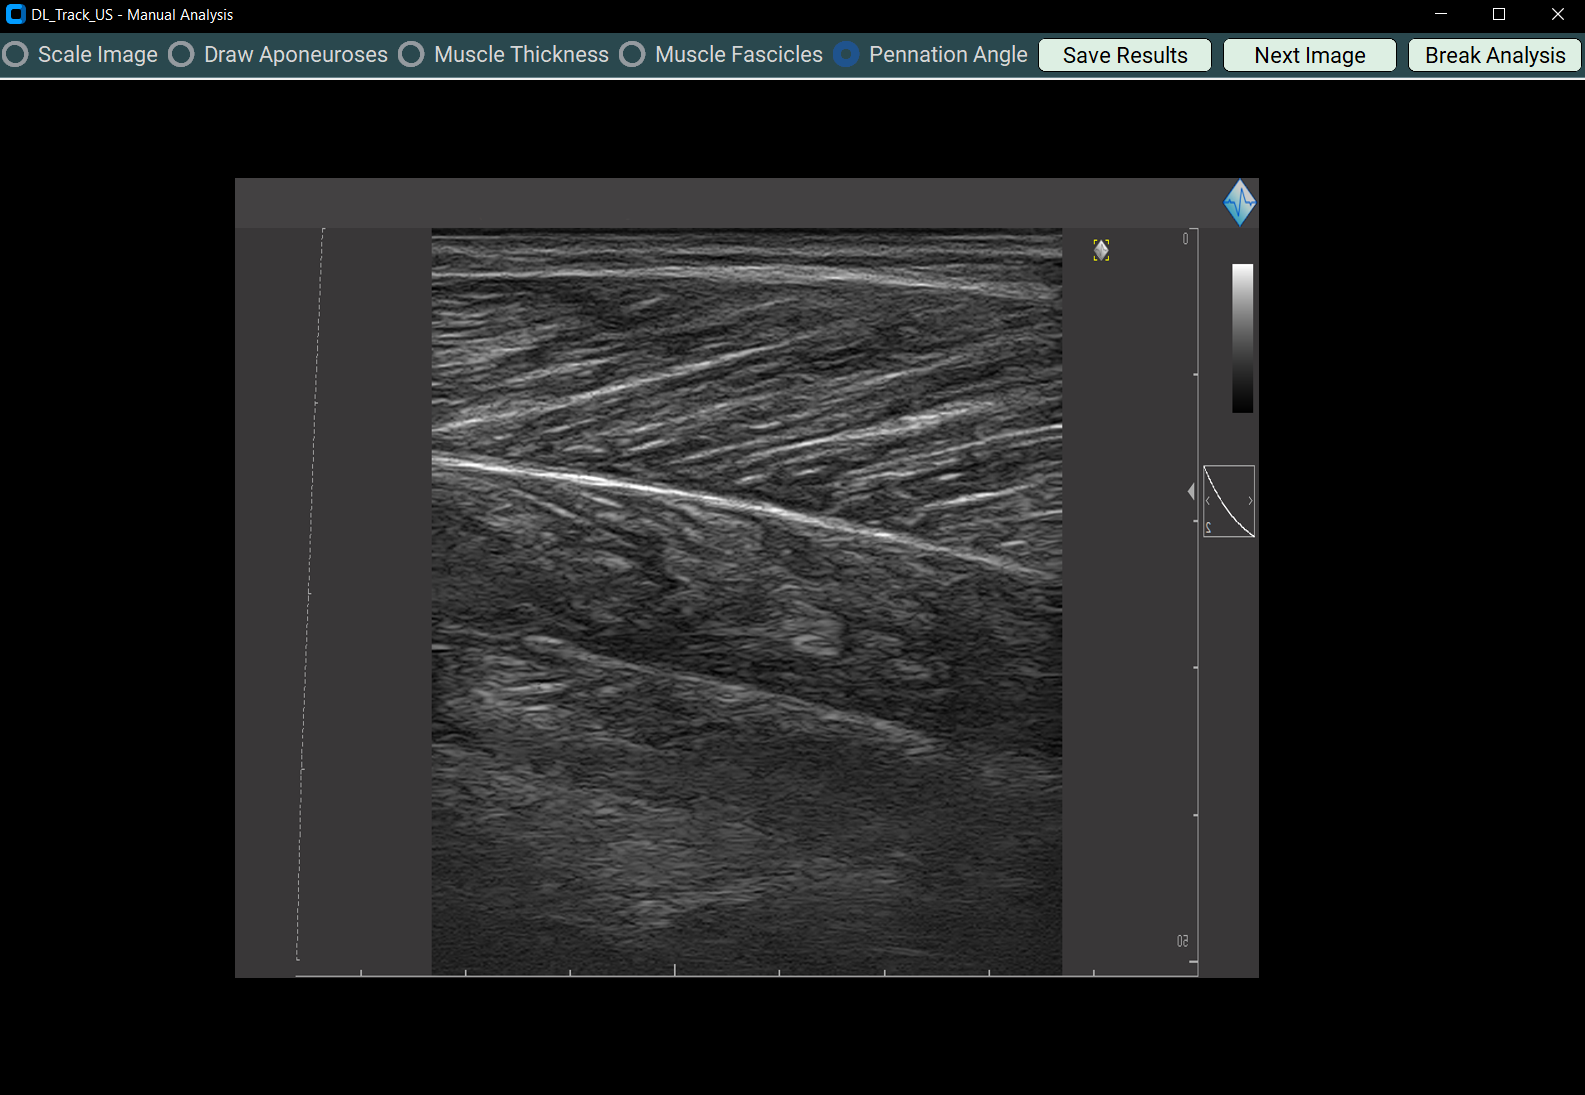

4.2 Drawing Aponeuroses¶

- Select Draw Aponeurosis to manually extend aponeuroses.

- A messagebox will instruct you.